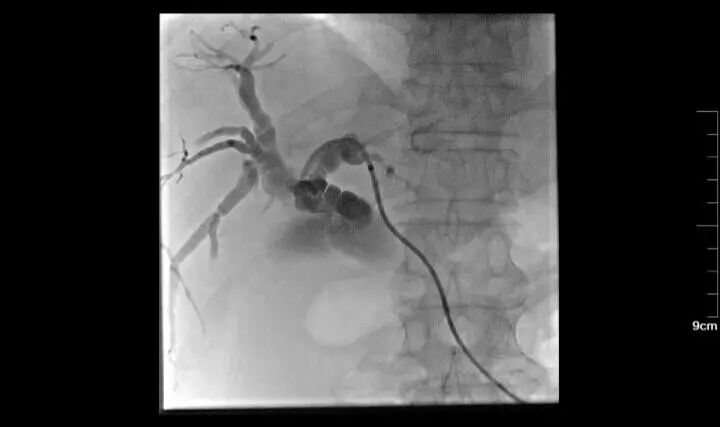

70歲女性,左肺鱗癌,失去手術(shù)及放療機(jī)會(huì),拒絕全身化療,多次行左肺支氣管動(dòng)脈灌注化療;帶瘤生存3年。

二 動(dòng)脈栓塞

腫瘤生長(zhǎng)需要由供血?jiǎng)用}提供營(yíng)養(yǎng)物質(zhì),介入醫(yī)生可以將特制的導(dǎo)管送至腫瘤的供血?jiǎng)用},然后通過(guò)導(dǎo)管注入栓塞物質(zhì),把腫瘤的供血?jiǎng)用}完全栓塞住,讓腫瘤沒(méi)有營(yíng)養(yǎng)供應(yīng),在實(shí)際工作中,常常把化療藥物與栓塞物質(zhì)混合,從而在栓塞血管的同時(shí)不斷釋放化療藥物持續(xù)殺死腫瘤細(xì)胞,效果更加顯著,就是老百姓常說(shuō)的把腫瘤餓死。

55歲男性,左肺鱗癌,行三次左肺支氣管動(dòng)脈灌注化療+栓塞術(shù)后,治療縮小,結(jié)合局部放療,病情控制可。